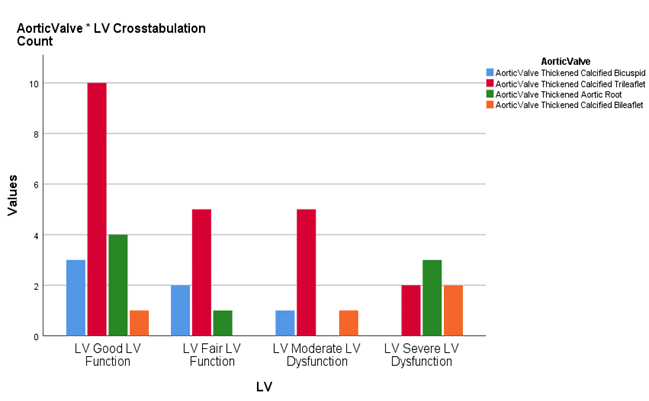

Feasibility of Computed Tomography Coronary Angiography in Diagnosing Left Ventricle Dysfunction in Patients with Aortic Stenosis

Aortic stenosis (AS) is a pathological condition in which the aortic valve, which is present between the left ventricle and...Read More